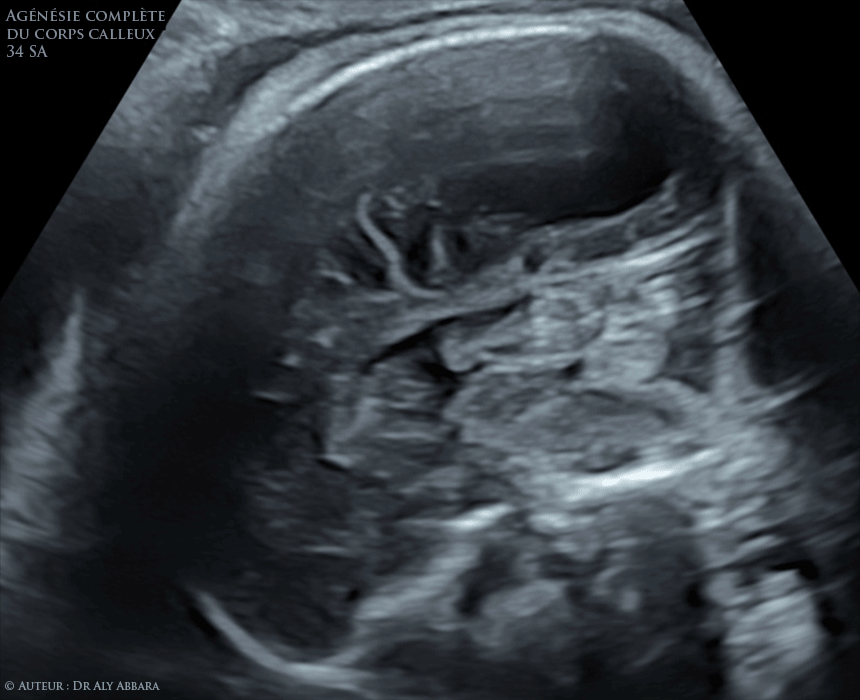

Le corps calleux se développe in utero entre la 10e et la e semaine de gestation L'agénésie du corps calleux est une malformation cérébrale congénitale qui correspond àL'autre, sans transition et sans adaptationAgénésie du coprs calleux, description et signes échographiques inutero puis présentation d'un cas d'agénésie partielle du corps calleux par une coupe échographique cérébrale sagittale médiane du cerveau chez un foetus triploïde (69,XXX)

Agenesie Complete Du Corps Calleux